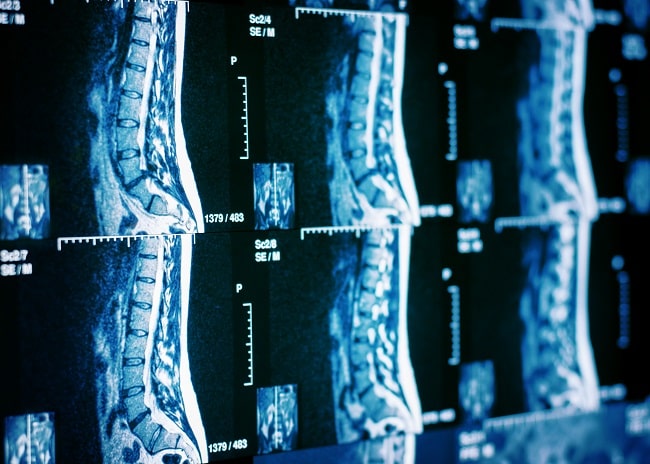

CT scan tulang belakang atau CT scan spine merupakan modalitas radiologi untuk penegakan diagnosis pada pasien dengan nyeri punggung bawah, patah tulang belakang, spondilitis TB, dan berbagai kelainan tulang belakang lain. Pemeriksaan CT scan dapat memberikan visualisasi yang mendetail terhadap struktur tulang, diskus intervertebralis, serta jaringan lunak tulang belakang.[1,2]

CT scan merupakan modalitas pencitraan lini pertama untuk mengevaluasi pasien trauma, terutama pada pasien dengan risiko tinggi mengalami cedera tulang belakang. Pemeriksaan CT scan juga berguna dalam mengevaluasi keadaan pascaoperasi, seperti verifikasi operasi fusi tulang belakang (spinal fusion), lokasi implan, serta identifikasi komplikasi.[2]

Pada kasus spondilitis TB, nyeri punggung bawah, dan spine curvature disorder, CT scan mampu memungkinkan identifikasi perubahan patologis seperti inflamasi pada tulang, sumsum tulang belakang, dan struktur saraf terkait. Dengan resolusi tinggi yang dimilikinya, CT scan mampu mendeteksi lesi, kerusakan tulang, dan kelainan anatomi lain dengan akurasi tinggi, yang merupakan langkah kunci dalam menegakkan diagnosis yang tepat dan merencanakan penatalaksanaan yang sesuai bagi pasien.[1-3]